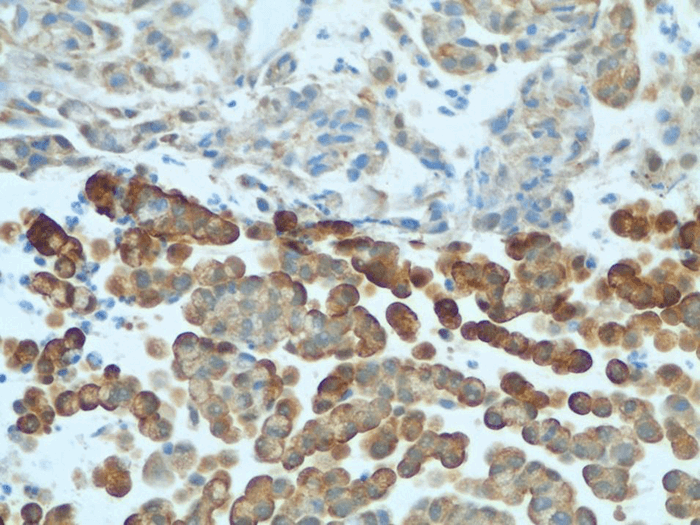

Pathologic examination revealed a 5 cm ulcerating mass extending into the subserosa of the ascending colon. Microscopically, the tumor demonstrated goblet cells arranged in an organoid fashion (Figure 1) with a mitotic index of 5/mm3 and a Ki-67 labeling index of 60%. It was assigned a Tang B classification.

Figure 2. Primary goblet cell carcinoid tumor staining positive for neuron-specific enolase